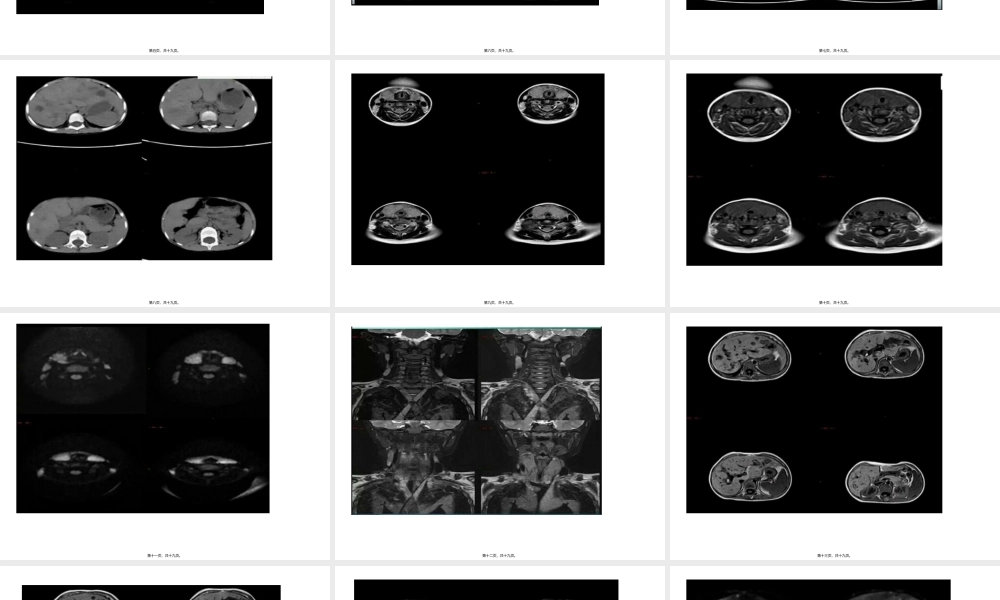

病例(bìnglì)分析第一页,共十九页。第二页,共十九页。影像(yǐnɡxiànɡ)表现第三页,共十九页。第四页,共十九页。第五页,共十九页。第六页,共十九页。第七页,共十九页。第八页,共十九页。第九页,共十九页。第十页,共十九页。第十一页,共十九页。第十二页,共十九页。第十三页,共十九页。第十四页,共十九页。第十五页,共十九页。第十六页,共十九页。第十七页,共十九页。病理:颈淋巴结活检病理:朗格罕斯细胞(xìbāo)组织细胞(xìbāo)增生症小结:朗格罕斯细胞(xìbāo)组织细胞(xìbāo)增生症(LCH)是一种少见的原因不明的肉芽肿性疾病,发病率约为0.5/10万~1/10万,可以是单一器官或多系统多器官受累,骨骼最为常见,其次为皮肤、中枢神经系统、肝胆和脾脏,肺、淋巴结、软组织、骨髓、腺体及胃肠道等。本病可发生于任何年龄,但50%以上病例发生于1~15岁儿童,发病高峰为1~4岁,男女之比约2:1。【影像学表现】1.骨骼:颅骨、股骨、脊柱及肋骨为常见发病部位,①活动期:表现为类圆形圆形或不规则形单囊或多囊状溶骨性破坏,患骨轻度膨胀,皮质可碎裂,形成软组织肿块,此期在病理上以嗜酸性粒细胞(xìbāo)及朗格罕氏组织细胞(xìbāo)增生为主。②修复期:表现为骨破坏减少,增生增多,长骨骨干可增粗,密度增高。2.肺部:早期病变在CT上以结节状表现为主,晚期则以囊疱状表现为主,结节直径多小于10mm,结节多位于两肺上叶,下叶基底段少见,囊疱为薄壁或厚壁,少部分相邻囊疱融合成不规则形,结节可以向囊疱转变,囊疱间肺组织轻度磨玻璃样密度增高。3.肝脏:朗格罕斯细胞(xìbāo)和炎性细胞(xìbāo)浸润引起门静脉周围炎症和水肿,表现为带状或结节状低密度影,增强后可见强化;易于侵犯胆管,致硬化性胆管炎,导致胆管扩张。4.中枢神经系统:①占位性病变:垂体和下丘脑是LCH最早最常见的中枢神经系统部位,临床上以中枢性尿崩症为首发症状,在MR上表现为垂体柄增粗,增强呈渐进性均匀强化,但病变也始于脑内任何一个部位的血管外膜,并逐渐形成肉芽肿样肿块。②变性性病变:可发生于小脑齿状核、基底节区及脑干对称性炎性病变。5.其他:发生于腺体及淋巴结,主要表现为体积增大;发生于肌肉等软组织在MR上表现为T1等或低信号,T2为高信号,增强扫描有较明显强化。第十八页,共十九页。内容(nèiróng)总结病例分析。病理:颈淋巴结活检病理:朗格罕斯细胞组织细胞增生症小结:朗格罕斯细胞组织细胞增生症(LC...